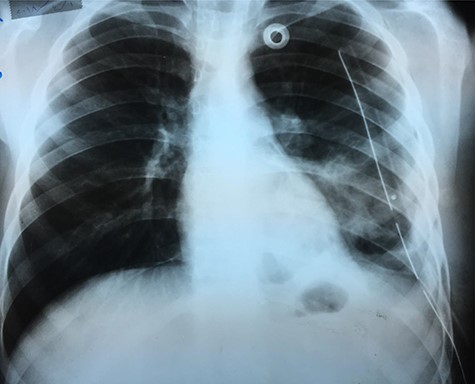

Chest X-ray (Fig. 1) showed an increased density in the left lower zone of the lung. Forty-eight hours later, the patient arrived at the ER along with the computed tomography (CT) scan (Fig. 2). He was in a very poor general condition with pallor, severe dyspnea and clouding of consciousness. Physical examination showed the absence of the left lung sounds, shifted apex beat of the heart to the right and a thready pulse and a blood pressure of about 80/40 mmHg.

A catheter was placed and fluid infusion began, and emergency thoracentesis showed fresh blood. Immediate exploratory thoracotomy was performed (Fig. 3). Three liters of blood were extracted, and the pleural adhesions were liberated. A diaphragmatic hernia was found, with an ischemic strangulated and perforated stomach. The stomach was freed, found vital, its perforation was repaired and it was returned to the abdominal cavity. The opening in the diaphragm was sutured and supported with the omentum. The lung was in good shape.